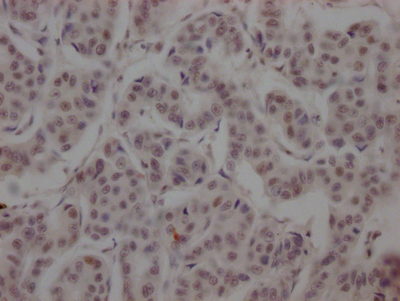

IHC image of CSB-RA152430A0HU diluted at 1:100 and staining in paraffin-embedded human breast cancer performed on a Leica BondTM system. After dewaxing and hydration, antigen retrieval was mediated by high pressure in a citrate buffer (pH 6.0). Section was blocked with 10% normal goat serum 30min at RT. Then primary antibody (1% BSA) was incubated at 4℃ overnight. The primary is detected by a Goat anti-rabbit IgG polymer labeled by HRP and visualized using 0.05% DAB.